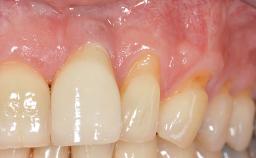

GBR and Soft-Tissue Augmentation Following Explantation to Rehabilitate a Soft- and Hard-Tissue Defect

It is sometimes necessary to remove and replace compromised implants. This case is a clear example of the need for multiple steps to achieve an optimal therapeutic result for patients with non-salvageable implants. It illustrates how the lost soft and hard tissues were rebuilt in a sequence that improved the healing of the hard tissues and assured their long-term stability. The 35-year-old healthy patient presented with clinical attachment loss on the proximal and lingual surfaces of the natural dentition. Some gingival recession was present on natural teeth, particularly in the posterior sextants (S1, S3, S4, and S6).

Soft Tissue Anatomy Intact Defective

Bone Volume Horizontally and vertically sufficient Horizontally deficient Deficient vertically or deficient vertically AND horizontally

Soft Tissue Contour and Volume Significantly deficient